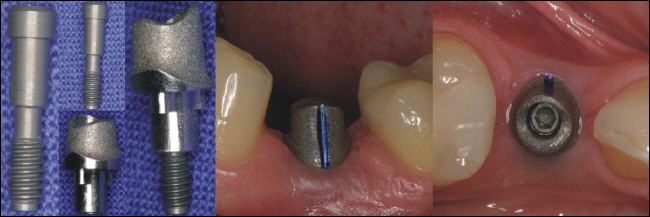

Die Verbindung Implantat-Aufbau

Die Verbindung zwischen dem Implantat und dem Aufbau (Interface) ist eine entscheidene Stelle für den form- und kraftschlüssigen Verbund der Teile. Sie sollte keine Bewegungen zulassen, eindeutig sein und rotationsschutz für den Aufbau bieten.

Einphasig oder Zweiphasig?

Einphasige Implantate=einteilige Implantate

Einphasige Implantate bestehen aus einem Stück und werden daher auch einteilige Implantate genannt. Im Gegensatz zu den zweiphasigen (zweiteiligen) Implantaten ist der Aufbau schon direkt ein festes Teil des Implantates und lässt sich nicht abschrauben.

Einteilige Implantate sind dafür konzipiert, dass sie sofort versorgt werden (Sofortversorgung).

Zweiphasige Implantate=zweitige Implantate

Bei den zweiphasigen Implantaten bestehen der Implantatkörper und der Aufbauaus zwei Teilen, die miteinander verschraubt werden. Der Aufbau wird erst nach der Einheilung des Implantates aufgeschraubt, weshalb man auch von zweiteiligen Implantaten redet.